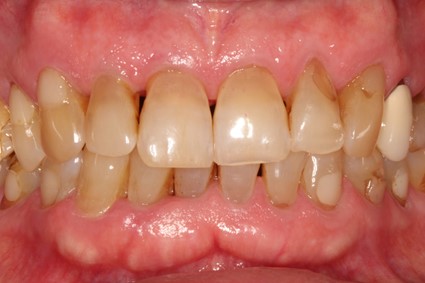

Métodos: Se llevó a cabo un caso clínico en una paciente de 40 años con fracaso de restauración fija dentosoportada en el incisivo central superior izquierdo, asociado a caries radicular subgingival con mal pronóstico restaurador. Tras la evaluación clínica y radiográfica, se indicó la exodoncia atraumática del diente afectado. Inmediatamente después, se realizó la colocación de un implante postextracción. El defecto periimplantario (gap) fue rellenado con un xenoinjerto óseo bovino. De forma simultánea, se llevó a cabo un injerto de tejido conectivo con el objetivo de optimizar el volumen y la estabilidad de los tejidos blandos periimplantarios. Se procedió a la colocación de una restauración provisional inmediata atornillada, diseñada para preservar el perfil de emergencia y guiar la cicatrización de los tejidos periimplantarios. Tras un periodo de cicatrización de cuatro meses, se colocó la restauración definitiva atornillada.

Resultados: El seguimiento clínico y radiológico evidenció una correcta osteointegración, estabilidad de los tejidos periimplantarios y un resultado estético satisfactorio, mantenido a los cuatro años.